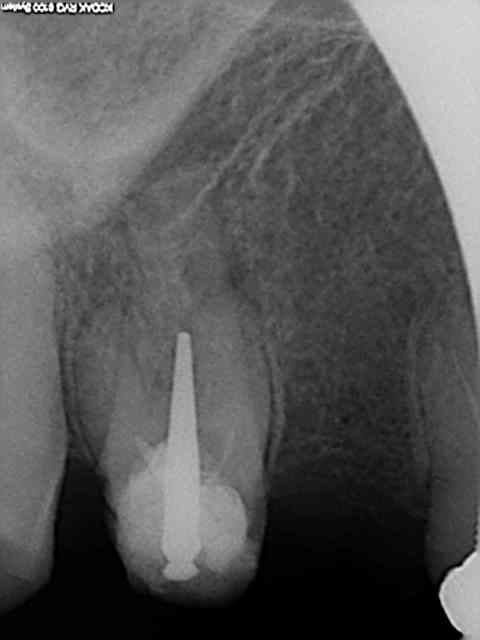

X ray 03 medium zvq18j - Eugenol